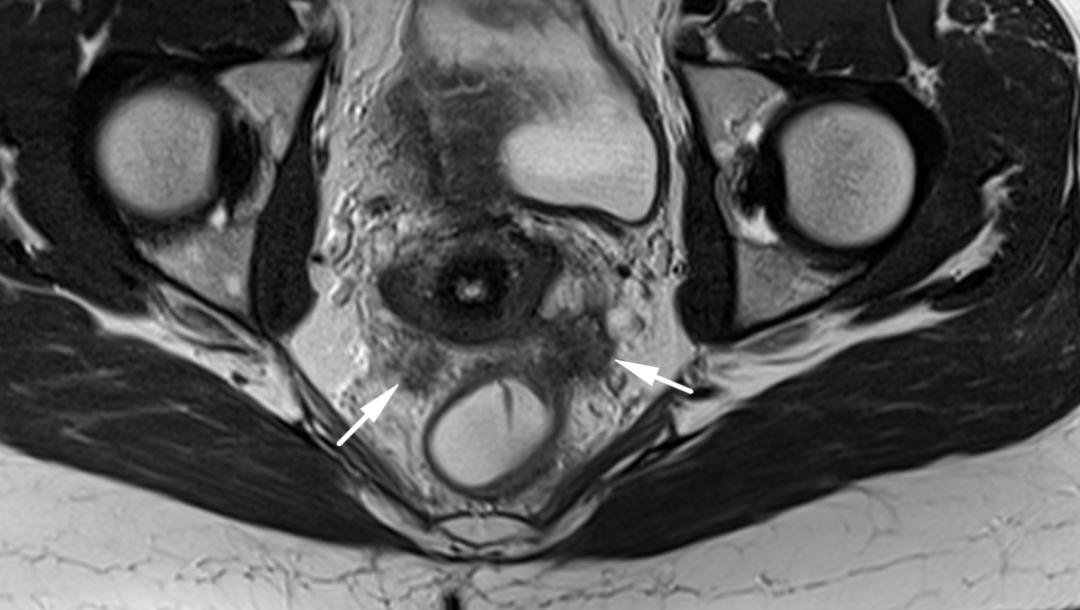

CASE 4

子宫内膜异位至双侧卵巢,T2WI 斜冠位和轴位双侧卵巢类圆形高低混杂信号结节,注意左侧卵巢子宫内膜异位症与乙状结肠之间线性低信号影,提示这些结构之间的粘连。